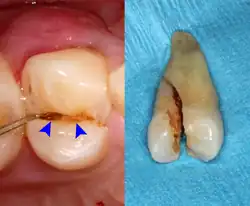

Gutta-percha point indicating abscess origin